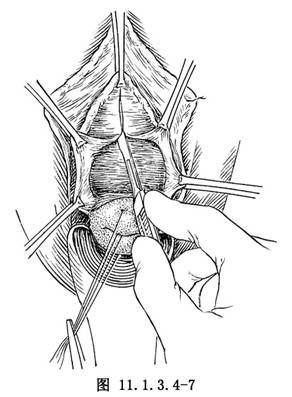

(1)自尿道外口下約1cm處開始,至子宮頸內口水平,切開陰道黏膜,注意避免損傷尿道、膀胱(圖11.1.3.4-7)。